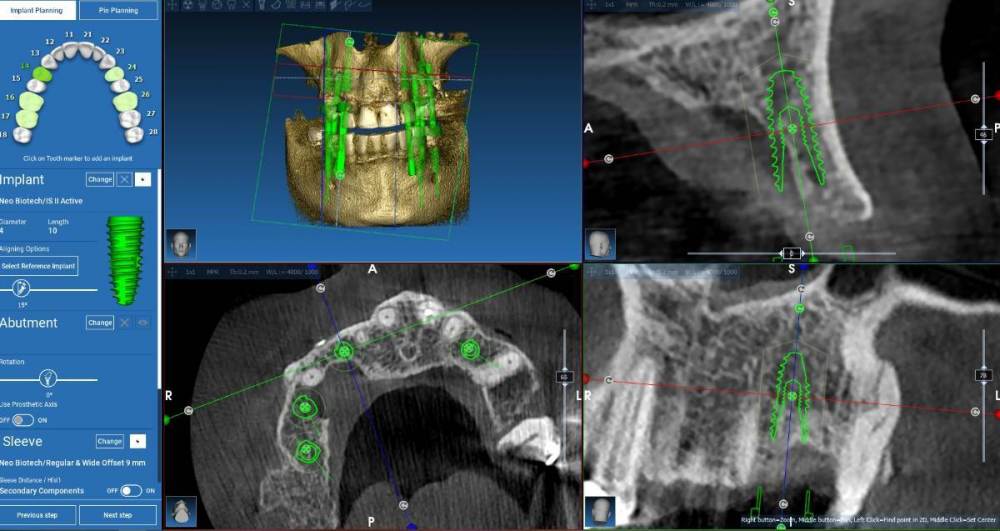

TIGER Опубликовано 27 ноября, 2023 Поделиться Опубликовано 27 ноября, 2023 @Fin постановку сделайте и поймёте Ссылка на комментарий

Fin Опубликовано 28 ноября, 2023 Автор Поделиться Опубликовано 28 ноября, 2023 19 часов назад, TIGER сказал: @Fin постановку сделайте и поймёте Уже немножко неактуально.Объяснил что пациенту надо делать НКР в любом случае и он пропал. Сейчас бы сделал,начал каждому пациенту делать постановку. 1 1 Ссылка на комментарий